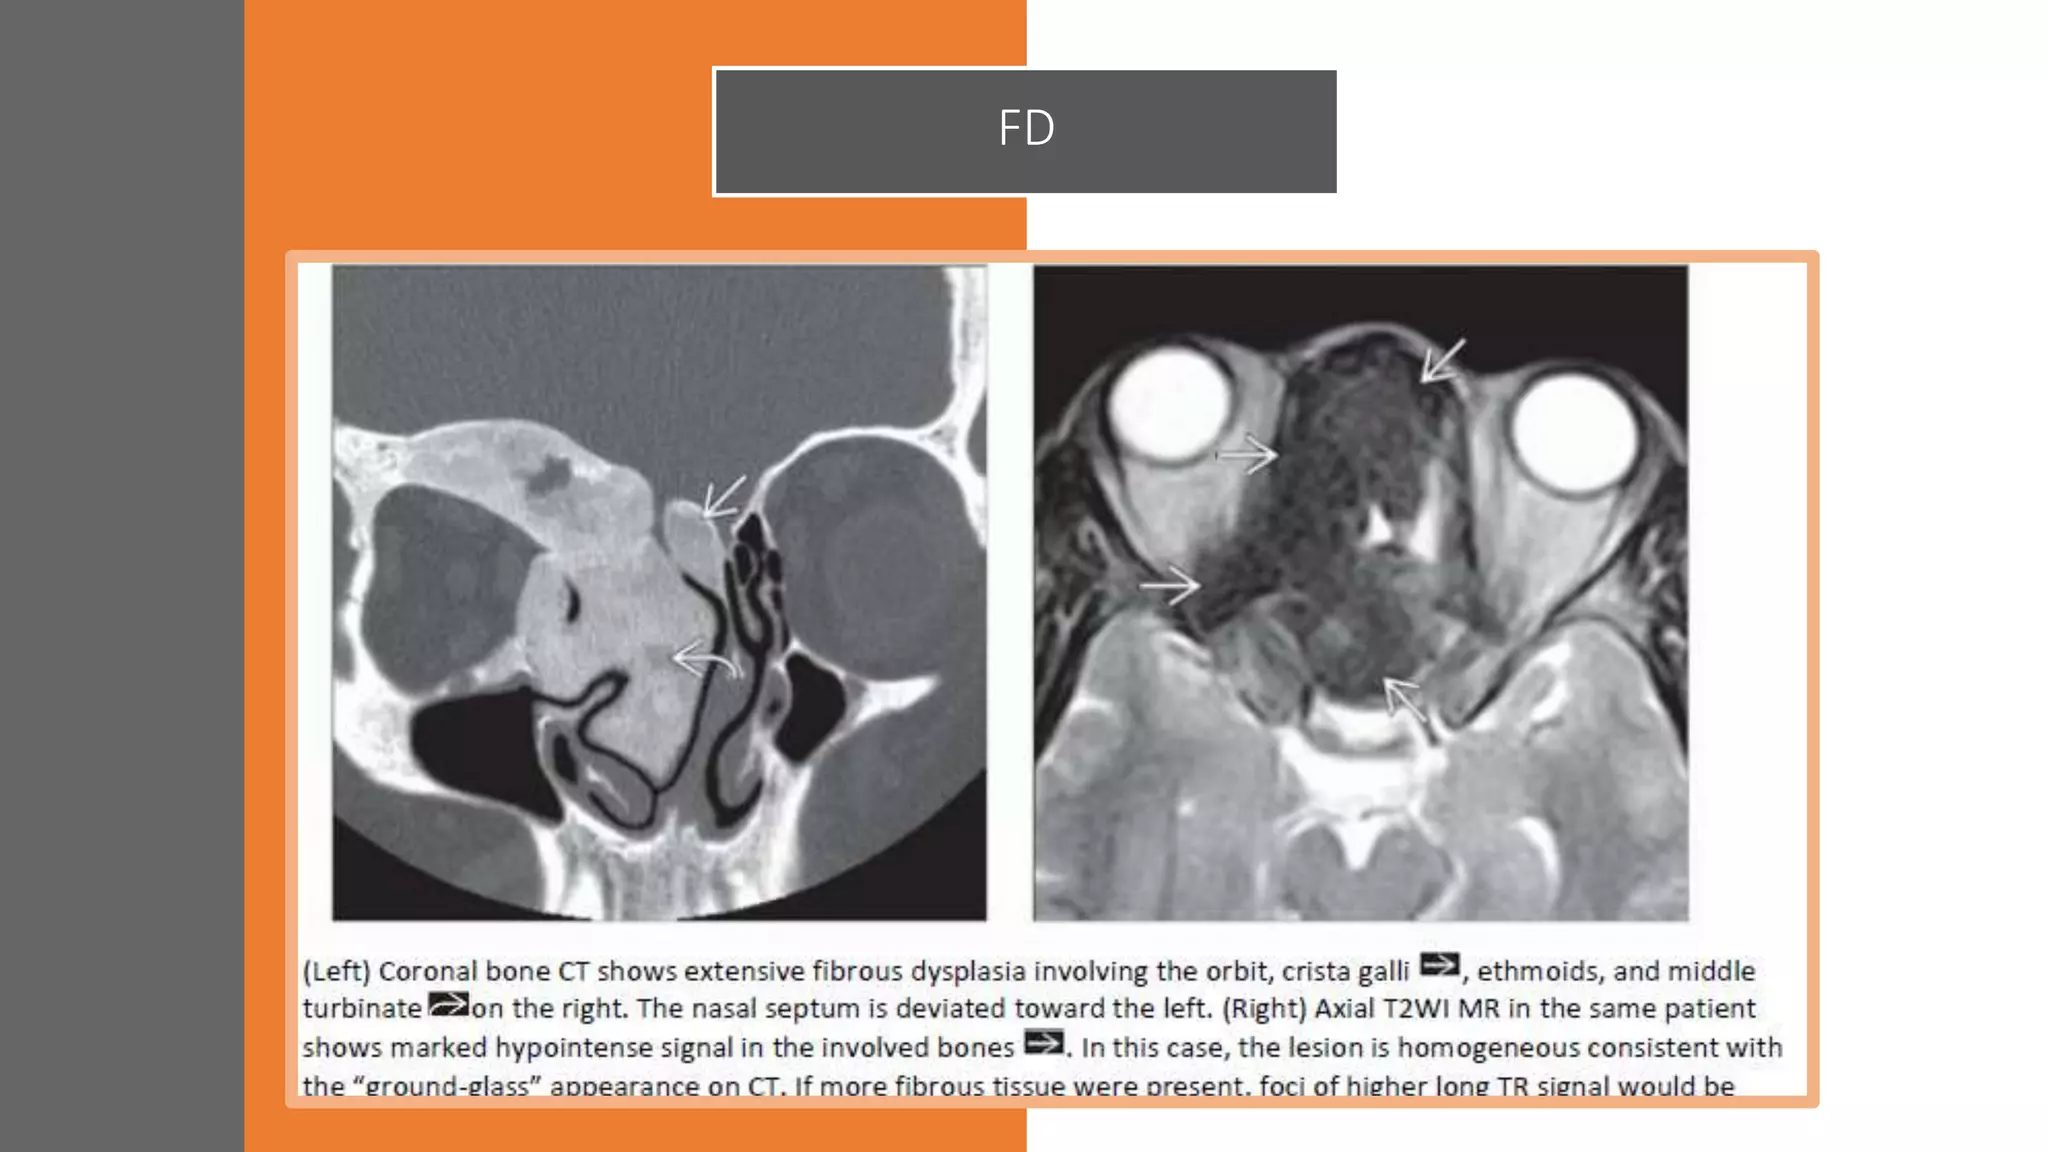

SINONASAL

FIBROOSSEOUS LESIONS

• Spectrum of disorder a purely fibrotic lesion

at one end and a dysplastic bony lesion at

the other

• Fibrous tissue replacing normal medullary

bone

• Diagnostic Clue

FD : Ill-defined expansion of diploic space with

“Ground-glass” density

Ossifying Fibroma : Well-demarcated,

expansile mass with soft tissue density

(fibrous) central area surrounded by ossified

rim

FD

SINONASAL FIBROOSSEOUS LESIONS • Spectrumof disorder a purely fibrotic lesion at one end and a dysplastic bony lesion at the other • Fibrous tissue replacing normal medullary bone • Diagnostic Clue FD : Ill-defined expansion of diploic space with “Ground-glass” density Ossifying Fibroma : Well-demarcated, expansile mass with soft tissue density (fibrous) central area surrounded by ossified rim

• #89 Expansion of left maxillary sinus wall with GGO

• #90 AKA Lichtenstein-Jaffe disease, leontiasis ossea, cherubism

• #91 AKA Lichtenstein-Jaffe disease, leontiasis ossea, cherubism